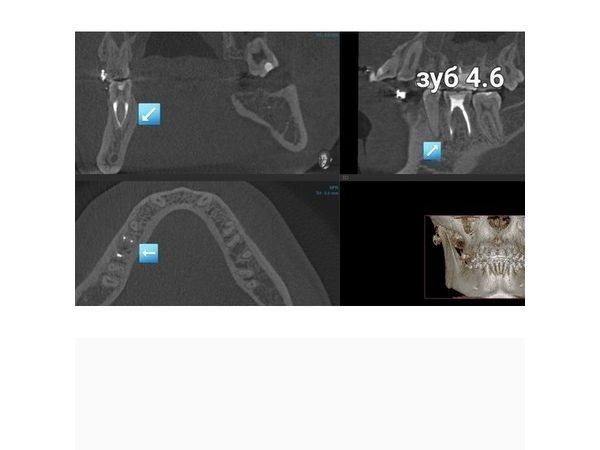

В области мезиального корня зуба 4.6 отмечался обширный очаг разрушения кости, который распространялся от верхушки корней до места их соединения, тень пломбировочного материала в мезиальных корневых каналах нечёткая и неоднородная, располагалась пристеночно, доходила до половины и второй трети каналов (мезиального и дистального).